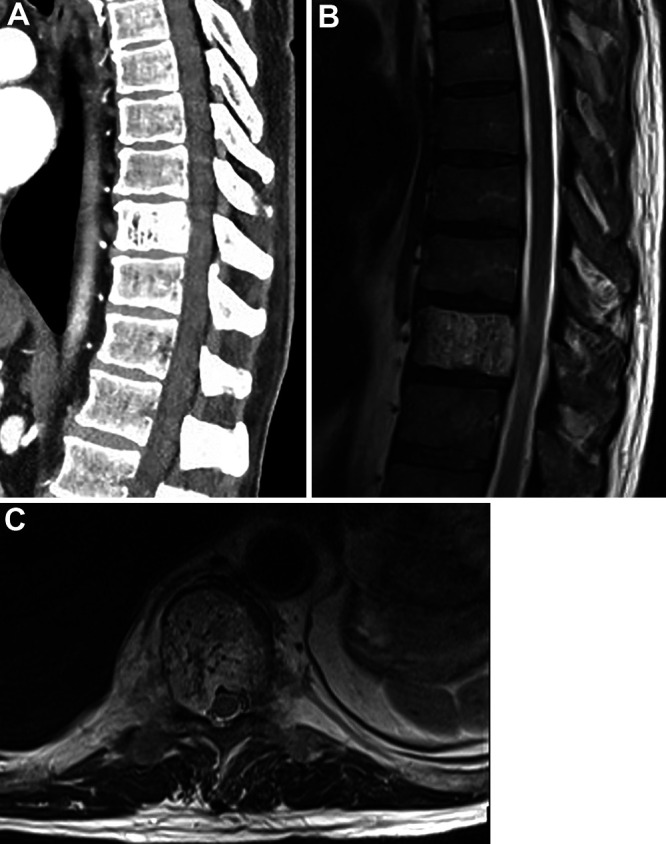

Observations: Here the authors report the first case of a T10 vertebral hemangioma treated with transpedicular Onyx embolization aided by a robotic platform that guided pedicle cannulation and Craig needle placement. An intravenous catheter was attached to the needle and dimethylsulfoxide was infused, followed by Onyx under real-time fluoroscopy. Repeat angiography demonstrated significantly reduced contrast opacification of the vertebral body without compromise of the segmental artery. A T9-11 pedicle screw fixation was performed to optimize long-term stability. The patient's symptoms improved and was stable at the 6-month follow-up.

Lessons: Transpedicular embolization of vertebral hemangiomas can be performed successfully under robotic navigation guidance, avoiding complications seen with the intra-arterial approach and allowing for simultaneous pedicle screw fixation to prevent collapse and delayed kyphotic deformity. During the same procedure, a biopsy specimen can be collected for pathology. This technique can help to alleviate patient symptoms while avoiding complications associated with transarterial embolization or open resection.